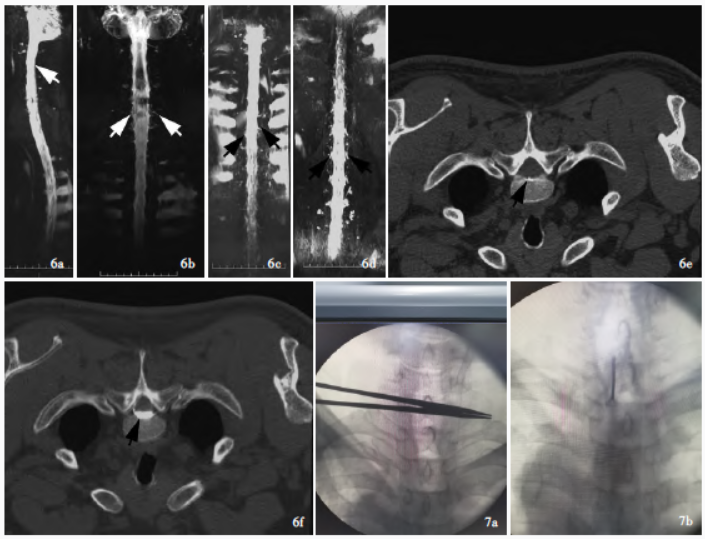

图6 入院后MRM(2021 年10 月26 日)和CT 脊髓造影(2021 年10 月28 日)检查所见,6a 侧位MRM 显示,C2、C4 ~ 5 椎体后方软组织内少量液性信号影(箭头所示) ,6b,6c 正位MRM 显示,C7 ~ 8、T1 右侧、T5 左侧、T6 ~ 7 脊神经根周围液性信号影(箭头所示) ,6d 正位MRM 显示,C5 ~ T1、T5 ~ L3 硬脊膜外液性信号影(箭头所示) ,6e 横断面CT脊髓造影显示,T2 椎体背侧骨赘形成(箭头所示) ,6f 横断面CT脊髓造影显示,T2 硬脊膜外对比剂积聚(箭头所示) ;图7 靶向自体血硬膜外血贴术(2021年11月1日)术前和术中所见,7a 术前定位椎体T1 ~ 2 ,7b 术中向硬膜外腔注射混有对比剂的自体血约40 ml

治疗1周后(10月21日)脑脊液压力

为145 mm H2O(1 mm H2O = 9.81 × 10-3 kPa,80 ~180 mm H2O;表1),脑脊液免疫球蛋白和血清IL-6水平下降(表2),头痛症状明显缓解,仅体位变化较大时轻微头痛。入院第16天(10月26日)行磁共振脊髓成像(MRM),可见多部位硬脊膜外积液,脊神经根周围积液,软组织内可见脑脊液积聚(图6a ~6d);入院第18天(10月28日)CT脊髓造影可见骨赘形成,多部位硬脊膜外对比剂积聚,考虑为T1 ~ 2活动性脑脊液漏(图6e,6f)。

于入院第21 天(11 月1 日)行靶向自体血硬膜外血贴术(图7),术中向硬膜外腔注入自体血约40 ml,术后2 天头痛症状消失;术后3 天(11 月4 日)脑脊液压力135 mm H2O(表1),CT显示双侧硬膜下血肿吸收,右侧额颞顶叶残留少量硬膜下血肿,无脑室受压(图8)。继续予以低分子量肝素0.80 ml/12 h抗凝治疗7天。出院前(11月9 日)再次复查脑脊液,压力为190 mm H2O(表1),脑脊液免疫球蛋白和血清IL-6 趋于正常(表2),共住院31 天,出院后遵医嘱服用达比加群110 mg/次(2 次/d)。随访至出院后2 个月,未再出现头痛,CT显示硬膜下血肿消失;出院后3 个月,MRBTI未见明确血栓征象,且增强扫描仅右侧顶叶硬脑膜呈轻度强化(图9),停用达比加群。